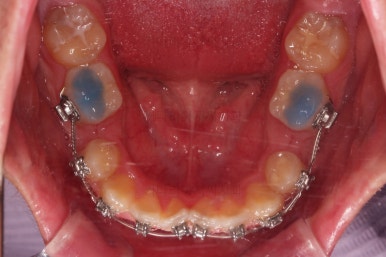

먼저 장치를 부착하고요.

환자분이 선택하신 장치는 자가결찰 메탈장치 입니다.

메탈이라고 모두 구시대적 장치는 아니에요. 자가결찰인지 아닌지가 구세대나 아니냐를 결정하는 기준이에요.

즉, 예를들면 자가결찰 메탈은 요즘세대, 그냥 세라믹은 구세대라 할 수 있어요.

자가결찰 중에서도 메탈도 있고 세라믹도 있는거고, 자가결찰 세라믹 중 클리피씨, 데이몬 클리어, 엠파워 클리어 등이 있습니다.

메탈은 강도가 높고, 부피도 작고, 위생관리에 약간의 장점이 더 있어요.

대신 보이는 측면에서의 단점이 있기 때문에 장단점을 고려해서 입맛에 맞게 선택하시라고 말씀 드리는 편이에요.

적절한 시기에 발치를 해주고요.

발치 공간을 이용해서 치열을 가지런하게 해줍니다.

가지런하게만 해도 발치공간이 거의다 없어져가요.